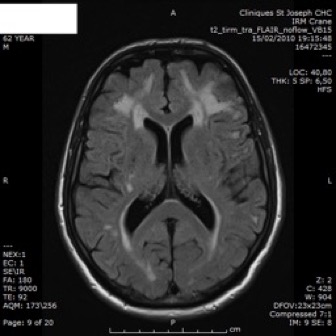

Axial FLAIR (A–C) and T2*GE (D)

- lésions lacunaires sous-corticales (B, flèche)